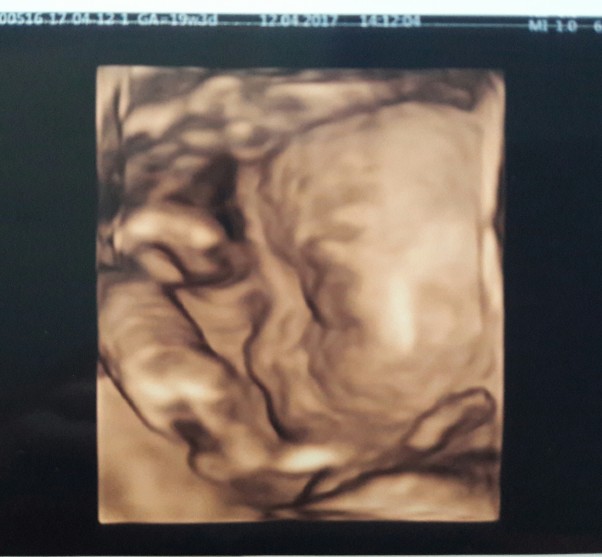

Skorzystałam z propozycji ginekologa i dokupiłam usg 4D na którym widziałam mojego żabusia w całej okazałości. Zasłaniał buźkę rączkami ale w końcu się odsłonił. Mój słodki synuś i ten jego nosek malusi :*